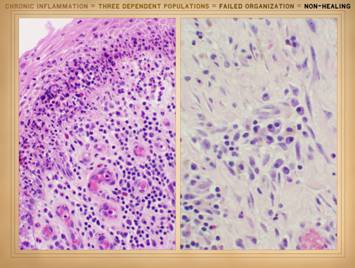

It should be clear by now that dynamical or thermodynamic stability may be in synch with or at odds with clinical desirability, but that a sick ulcerating wound is nonetheless a stable attractor.  This raises the inevitable question, why then does the CAP wound get into a state of dynamical stability even if that state is counter-productive to health?  If the control loop is supposed to work toward restoring a reference, why does it become complacent about an unconverged status?  This has already been answered in part – it is inherent in the principles of non-linearity, chaos, and attractors.  At this point though we need to acknowledge the actual physical structure or biological components of the wound.  It is a set of cells.  In Part 2 we saw that when wounds become auto-immunized and pathological, that the normal two cell populations of the healthy wound, acute inflammation and wound module, are joined by a third population, chronic inflammation.  As we discussed on slides 2 & 3 of this section, the wound as an organ is defined by its cell populations.  To understand how these populations interact and either succeed or fail to restore a stroma, we must now look at another aspect of non-linear dynamics: population logistics.